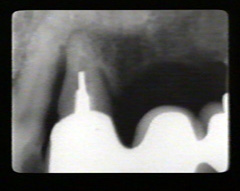

Las radiografías periapicales muestran pérdida de hueso alveolar en aproximadamente la mitad de la longitud de la raíz. La pérdida de hueso en el área de furacación se indica por la radiolucidez aumentada en la unión de las raíces en la región cervical.

En mesial del lateral derecho como en distal del central derecho aparece una perdida considerable de hueso. El puente fué realizado hace unos seis años como consecuencia de un accidente automovilístico.